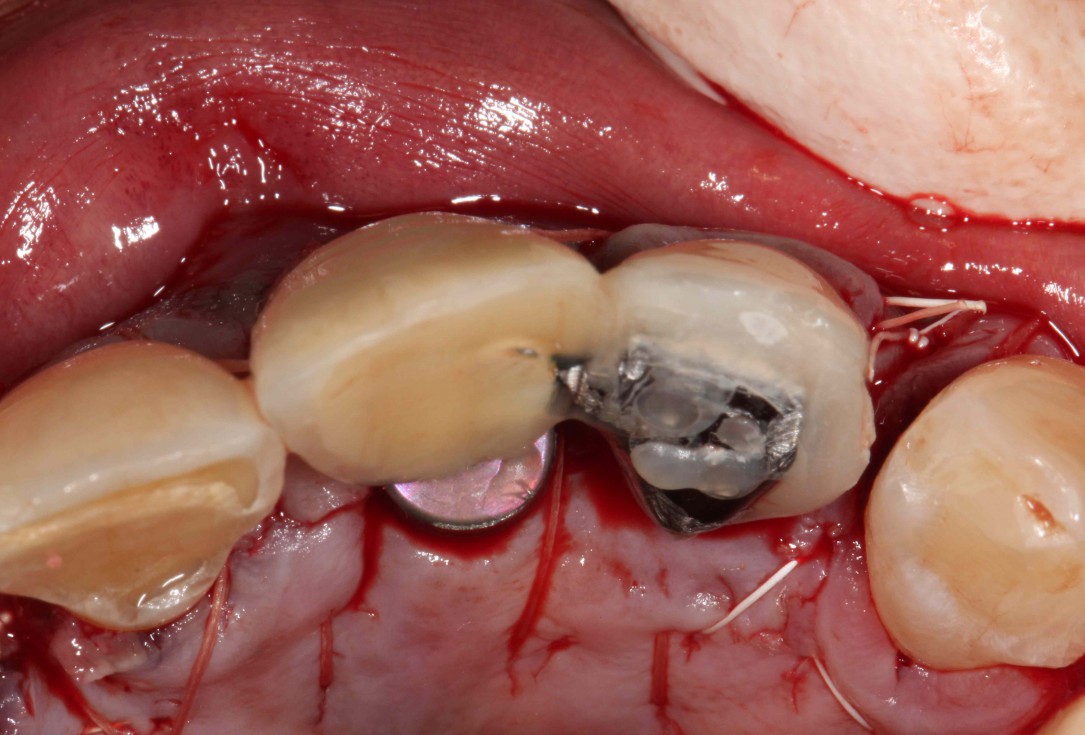

02/19 - Elevation of a buccal mucoperiosteal flap

GBR with cerabone® and Jason® membrane in the front tooth region - Dr. H. Maghaireh